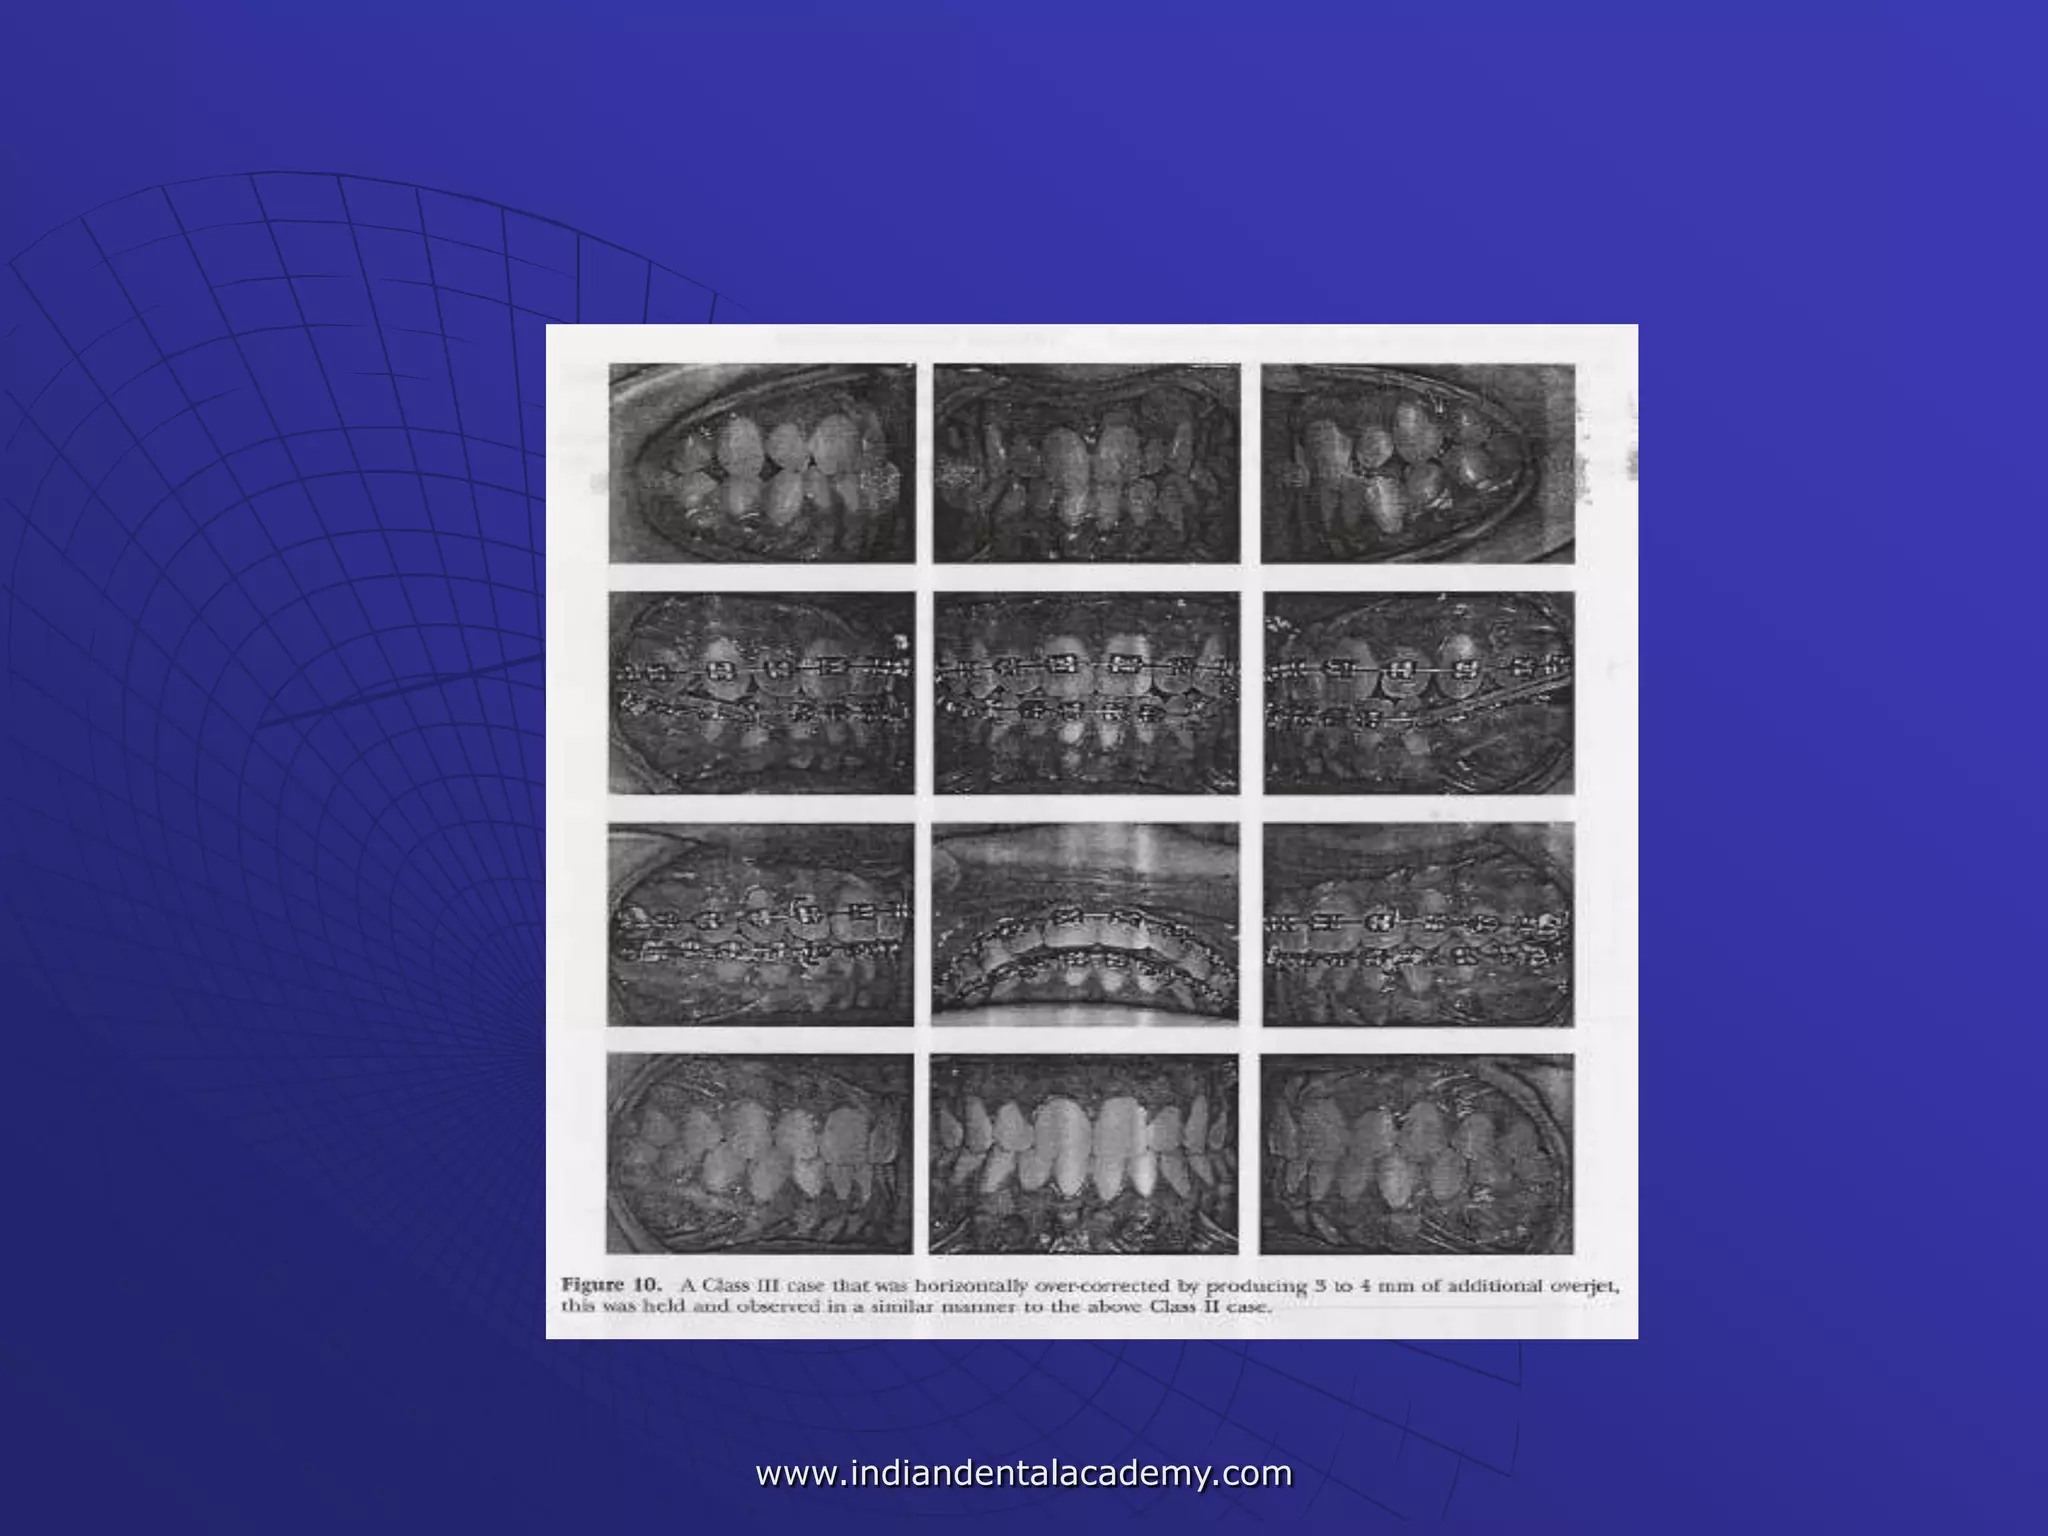

 Class III cases - horizontally over-corrected -producing 3 to

Class II cases (Fig 10).